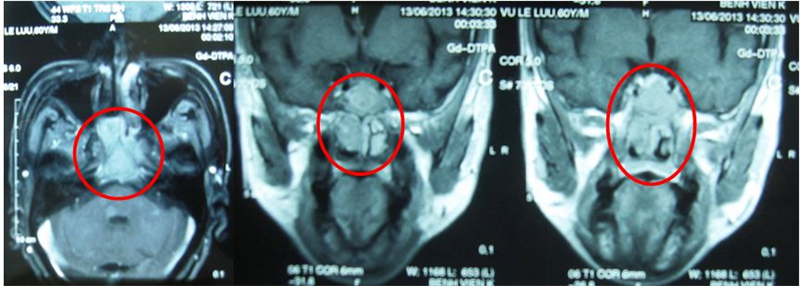

- Chụp MRI vòm họng.

Hình 2. Hình ảnh MRI trước điều trị: khối u vòm họng xâm lấn xoang bướm (vòng tròn).